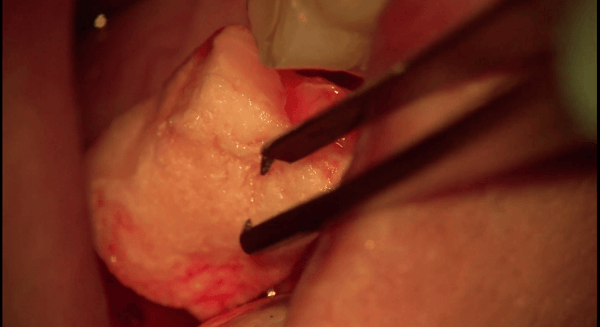

The Osteogen Bone Block is a malleable block that can be used for onlay grafting and ridge augmentation procedures. It is adaptable to the contours of defect site. Similar to the Osteogen Plug and Osteogen Strip, the Osteogen Bone Block infuses the bone graft into the collagen, eliminating the hassle and time spent mixing and packing particulate grafts while also eliminating the potential for graft wash out.

- For use in onlay grafting and ridge widening procedures, especially where the tenting technique is used.

- Perfect for sticky bone (see video below).